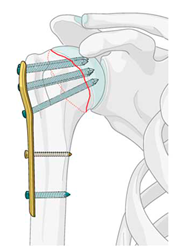

Остеосинтез титановой пластиной

Остеосинтез титановой пластиной — это хирургическая операция по лечению сложных переломов, при которой титановые пластины и винты используются для фиксации костных фрагментов в правильном положении. Этот метод обеспечивает надежную неподвижность кости, способствуя ее сращению.

Пластина обычно устанавливается на поверхность кости (накостный остеосинтез) и остается на месте до полного сращения, после чего может быть удалена. Чаще всего проводится остеосинтез титановой пластиной для большеберцовой, малоберцовой, лучевой костей.

Операция проводится для обеспечения надежной фиксации костных отломков после переломов, что необходимо для их правильного и быстрого сращения, особенно в случаях оскольчатых, смещенных или внутрисуставных переломов, а также при наличии риска повреждения мягких тканей или сосудов. Титановые пластины также используются для реконструкции и замены поврежденных участков костей, например, при переломах черепа или суставов, обеспечивая стабильность и функцию.